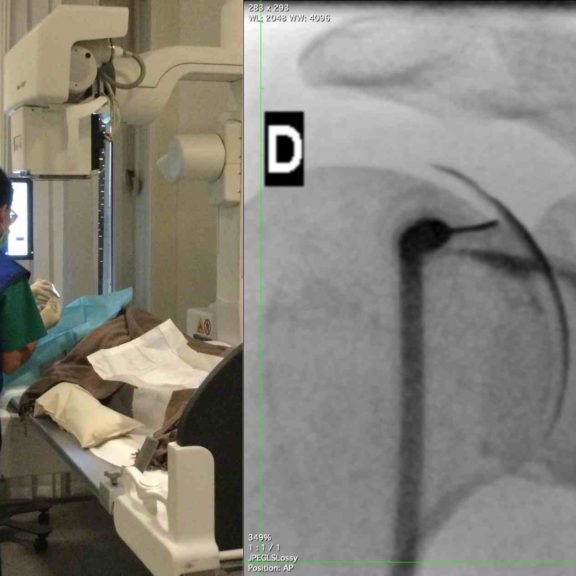

Capsulite rétractile de l’épaule : une prise en charge globale pour soulager les douleurs

Soulager la capsulite rétractile de l’épaule grâce aux infiltrations et une prise en charge physiothérapeutique.